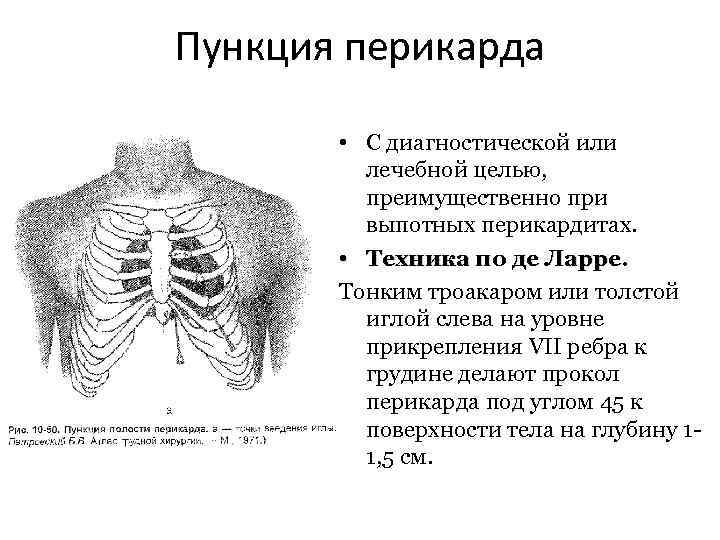

Пункция перикарда • С диагностической или лечебной целью, преимущественно при выпотных перикардитах. • Техника по де Ларре. Тонким троакаром или толстой иглой слева на уровне прикрепления VII ребра к грудине делают прокол перикарда под углом 45 к поверхности тела на глубину 11, 5 см.

Пункция перикарда • С диагностической или лечебной целью, преимущественно при выпотных перикардитах. • Техника по де Ларре. Тонким троакаром или толстой иглой слева на уровне прикрепления VII ребра к грудине делают прокол перикарда под углом 45 к поверхности тела на глубину 11, 5 см.